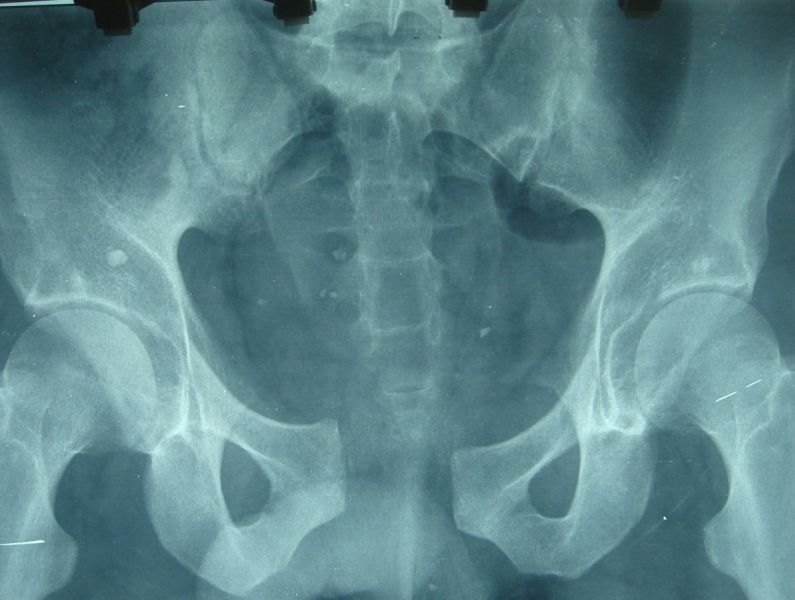

4. Posterior dislocation of the right hip with posterior acetabulum fracture in a 40-year-old male.

Treatment: 1st stage; closed reduction of the dislocation 2nd stage; open reduction of the acetabulum fracture with internal fixation

Ι. Obturator view of the right acetabulum shows the dislocation of the right hip II. Obturator x-ray right acetabulum shows the reduction of the hip, the red arrow shows the fracture III. Iliac x-ray acetabulum after the procedure shows the implant work (the patient referred to Mr. Antonios Papasotiriou who fixed the acetabulum)